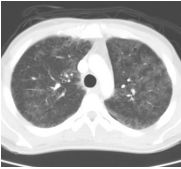

4. 39 y/o female, productive cough for 2 months